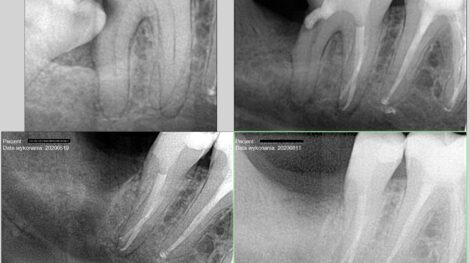

Powtórne leczenie kanałowe z zakrzywionym kanałem